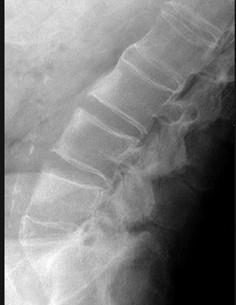

男,48岁,背痛,四肢强直,请结合影像图像,选择最可能的诊断 ( )A、骨脓肿B、骨软骨瘤C、压缩性骨折D、骨囊肿E、强直性脊柱炎

问题 男,48岁,背痛,四肢强直,请结合影像图像,选择最可能的诊断 ( )

选项 A、骨脓肿 B、骨软骨瘤 C、压缩性骨折 D、骨囊肿 E、强直性脊柱炎

答案 E